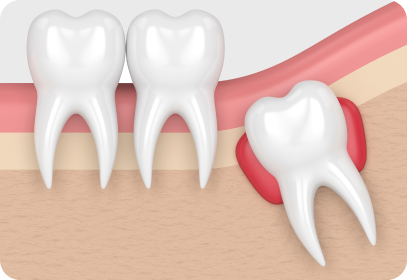

img-0501-3-1.jpg

수직으로 솟은 사랑니

가장 안쪽에 있는 사랑니는 칫솔이

잘 닿지 않아 관리가 어려워 충치나

잇몸 질환이 생기기 쉽습니다.

img-0501-3-2.jpg

가로로 나온 사랑니

바로 앞 어금니 뿌리를 압박해 염증을

일으키거나 턱뼈의 신경까지 손상시킬

수 있어 발치하는 것이 좋습니다.

img-0501-3-3.jpg

불완전 돌출 사랑니

비정상적인 위치에 매복되어 자란 사랑니는

염증과 통증을 일으킬 수 있으므로

발치하는 것이 좋습니다.